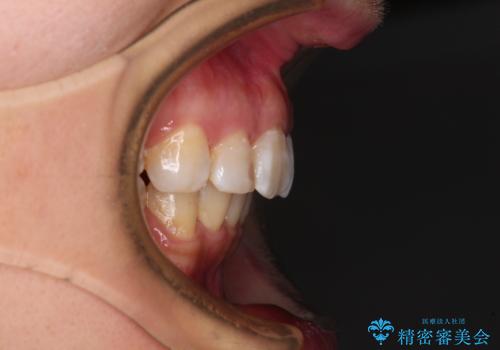

- 口元の閉じにくさと、前歯のでこぼこの歯並びを気にして来院された患者様です。

口元を積極的に引っ込めるために、上下左右の小臼歯計4本を抜歯することとしました。

咬み合わせが深く、咬合力強いため、補助装置を使用しながら積極的に口元を下げることとしました。